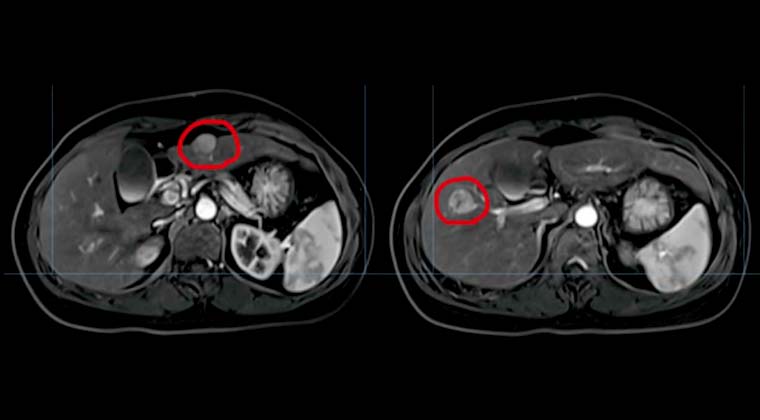

③ Случай 3:

Пациентка: Женщина, 46 лет

Диагноз: Рак печени

План лечения: 4D моделирование и локализация; очаги в сегментах S2 и S3 облучены суммарной дозой 50 Gy, 10 Gy за фракцию, 5 фракций.

Предлечебное МРТ в нашей больнице 012020:

Множественные узлы в сегментах S2, S3 и S5 печени; высокая вероятность малого рака печени.

Гемангиома печени в сегменте S

Контрольное МРТ 102021:

Изменения после комплексного лечения рака печени; очаги значительно уменьшились по сравнению с предыдущим обследованием.

Аденомиоматоз желчного пузыря, в целом без изменений.

До лечения:

После лечения: